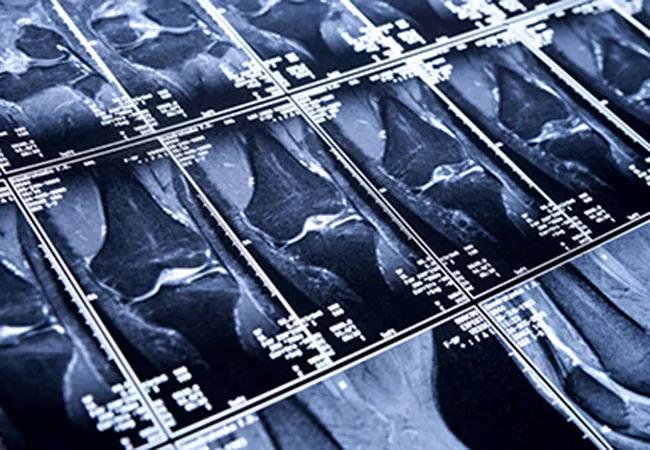

Her new, quantitative magnetic resonance imaging (MRI) methods — a refinement and improvement over traditional MRI techniques — are slated to more quickly and efficiently classify at-risk patients, which may allow physicians to intervene earlier with behavior modification or other treatments to prevent or delay OA symptoms.

OA is a common and sometimes debilitating disease that affects more than 27 million people in the United States and often manifests in the knee. Clinical imaging evaluation of OA has relied primarily on plain radiography, which only depicts bone-related changes that occur late in the disease. Unlike plain radiography, MRI is a powerful modality for evaluating soft tissues such as cartilage and menisci.

While significant efforts have been made in the past decade to develop quantitative MRI to detect early tissue degeneration in OA, existing methods are time-intensive and costly, and the equipment’s capabilities often vary with different manufacturers.

To bypass the traditional limitations of MRI in diagnosing OA, Dr. Li and her team are building on the premise that specific cartilage measurements (called MR T1p and T2 measurements) provide a more sophisticated and sensitive method to assess biochemical changes within the cartilage matrix, and may be promising biomarkers for early cartilage degeneration. Dr. Li’s team plans to develop new, accelerated T1ρ and T2 imaging methods and will test them on MRI systems from three manufacturers at four sites.